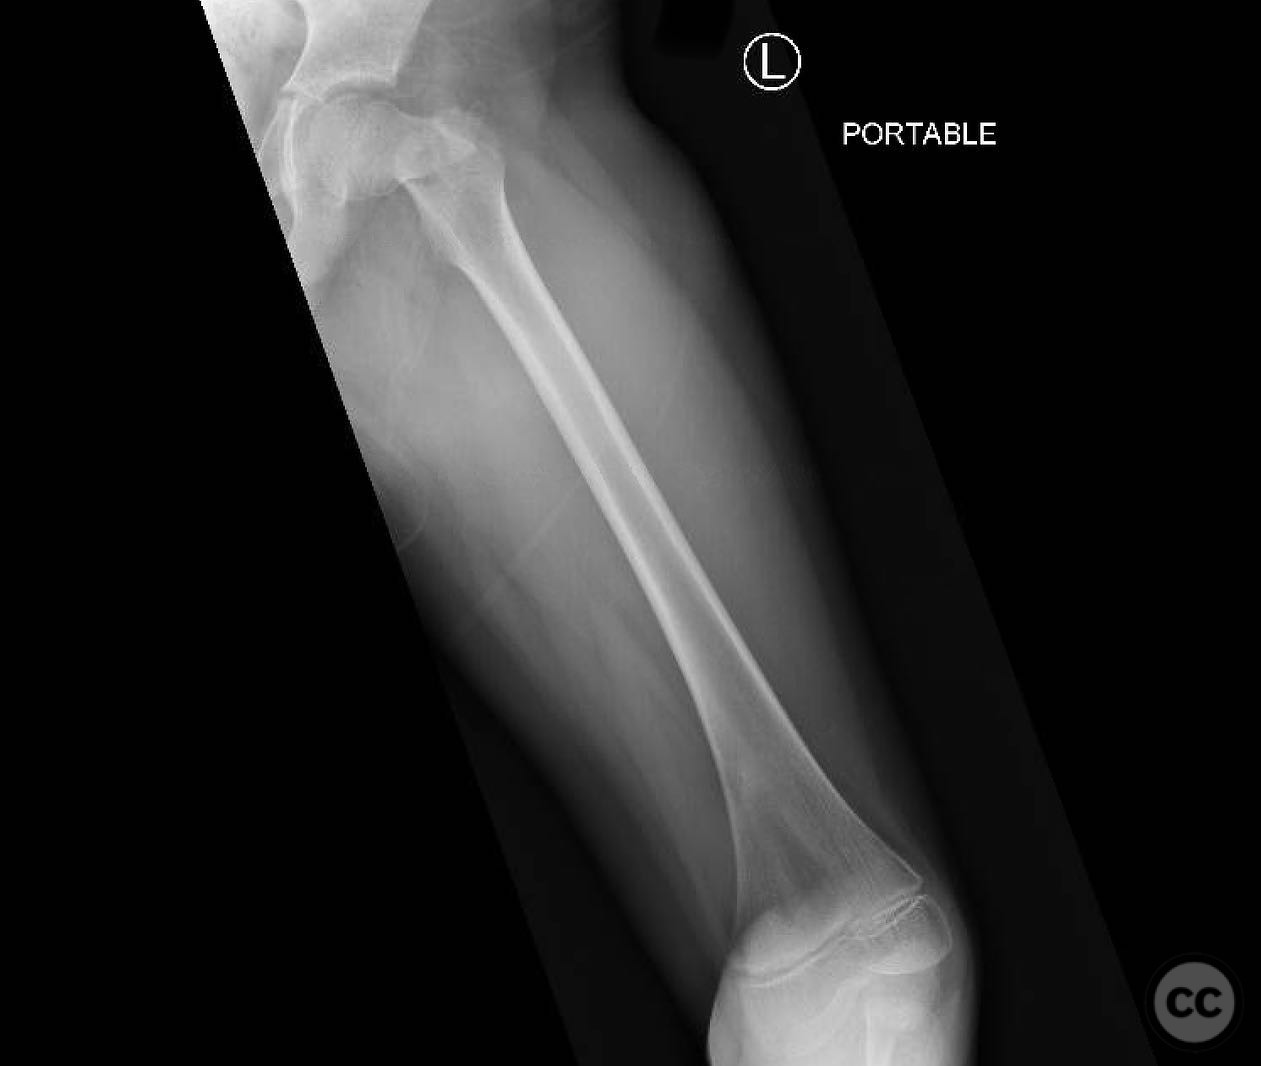

Clinical and radiological findings:  An 8-year-old boy fell approximately 15 feet from a treehouse, sustaining a displaced femoral neck fracture. There were no associated injuries to the head, spine, chest, or abdomen. The initial radiological assessment confirmed a displaced fracture of the femoral neck. Neurovascular examination was unremarkable.

Planning remarks:  The preoperative plan involved achieving a direct anatomic reduction and stable fixation of the femoral neck fracture. The surgical approach considered was a modified Smith-Petersen approach for optimal visualization and reduction, followed by a separate lateral approach for implant application.